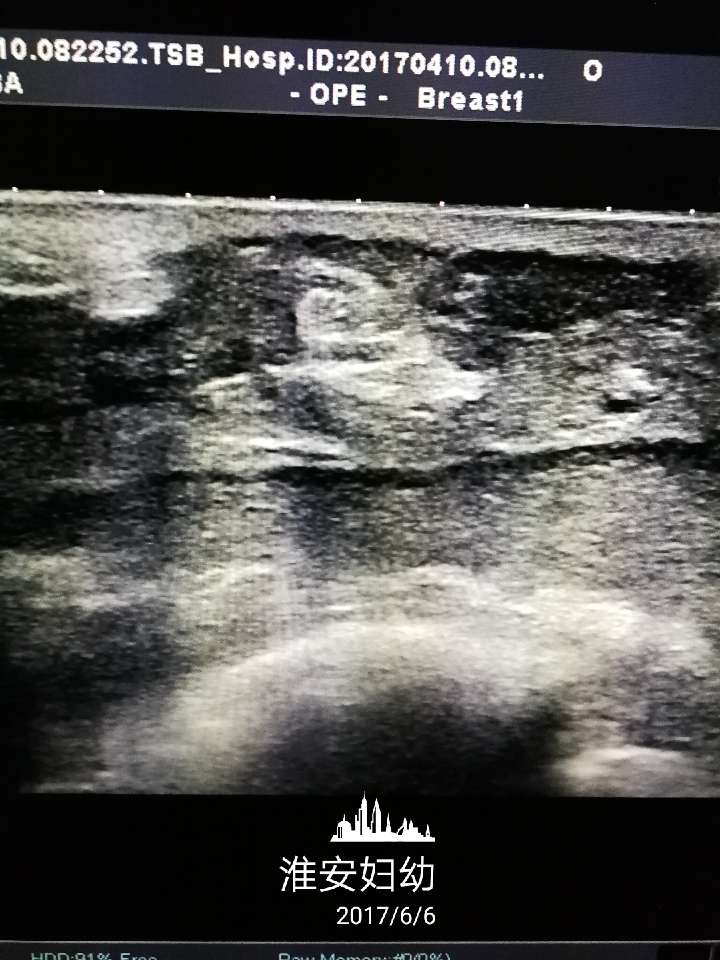

要根据患者的症状、体征、彩超、核磁共振以及粗针穿刺活检病理等结果明确诊断,同时排除乳腺癌、乳腺结核等病。